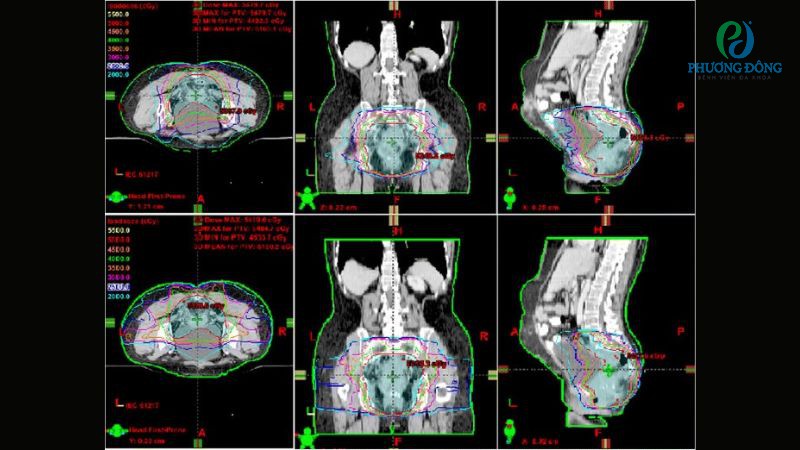

- Bước 3: Lập kế hoạch xạ trị dựa trên kết quả chụp hình ảnh, kỹ thuật viên, bác sĩ ung bướu sẽ làm việc với nhau để tính toán chính xác liều lượng, hướng tia và thời gian chiếu xạ tối ưu.